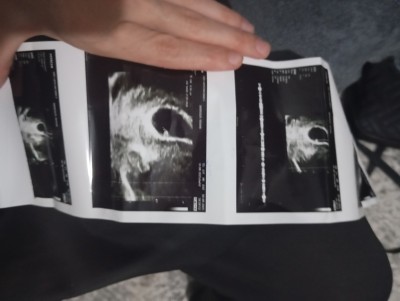

Pazartesi günü Sultanbeyli devlet hastanesine gittim kalp atışı için küçük daha dedi on gün sonra gel dedi bugün Sultanbeyli saygı Hastanesi'ne gittim özele  kalp atışı duydum çok güzel maşallah kese de Yuvarlak acaba cinsiyet kız mı 🥰

Gebelik haftası 6+2